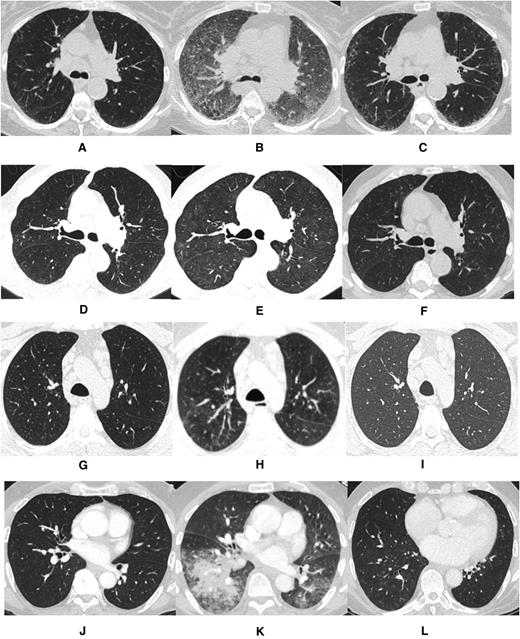

Computed tomography imaging for each case prior to ibrutinib exposure, during pneumonitis while on ibrutinib, and following ibrutinib discontinuation. (A,D,G,J) Pre-ibrutinib; (B,E,H,K) during ibrutinib; (C,F,I,L) post-ibrutinib.

The first case describes a 71-year-old woman with del(17p) del(11q)-positive relapsed CLL who was treated with ibrutinib at 420 mg daily 9 years after initial diagnosis. Prior therapy included fludarabine and rituximab. One month following ibrutinib initiation, she was hospitalized with dyspnea and hypoxia. Infectious workup was negative. A computerized tomography (CT) scan of the chest revealed widespread interstitial ground glass opacities not noted on CT imaging obtained 4 weeks prior to ibrutinib exposure (Figure 1A-B). Transbronchial biopsy and cytology revealed fragments of alveolated lung parenchyma with chronic interstitial inflammation and organization associated with loosely formed nonnecrotizing granulomas without evidence of viral infection or malignancy (Figure 2). Prednisone, at 40 mg daily, was initiated. The patient improved within 1 week, and ibrutinib was resumed at 420 mg daily on discharge. Three months following discharge, a CT scan of the chest demonstrated resolution of ground glass opacities (Figure 1C). Ten months following her initial hospitalization, the patient presented with dyspnea and increased sputum production without fever. An infectious workup was negative. A CT scan of the chest revealed centrilobular emphysema and superimposed peripheral reticular interstitial lung disease consistent with pulmonary fibrosis. Ibrutinib was held, and prednisone, 30 mg daily, was initiated. The patient improved and was discharged on steroids; ibrutinib was permanently discontinued.

The second case involves a 73-year-old man with del(11q)-positive relapsed CLL who was treated with ibrutinib at 420 mg daily 15 years after initial diagnosis. Prior CLL therapies included rituximab, fludarabine-cyclophosphamide-rituximab (FCR), rituximab-bendamustine (BR), ofatumumab, and anti-CD19 autologous chimeric antigen receptor T cells. Four months after initiating ibrutinib, the patient was hospitalized for dyspnea. A chest CT scan revealed diffuse ground glass opacities, absent in a CT scan performed before ibrutinib exposure (Figure 1D-E). Patchy areas of consolidation in the left lower lobe suggested stable chronic low-grade aspiration. Transbronchial biopsies revealed bronchial mucosa and alveolated lung parenchyma with reactive lymphoid infiltrate and organizing pneumonia with occasional eosinophils and neutrophils. Cytology revealed acute inflammation without evidence of malignancy or infectious etiology. Ibrutinib was discontinued, and prednisone 60 mg daily was administered for possible pneumonitis secondary to ibrutinib exposure. The patient experienced marked improvement, and ibrutinib was permanently discontinued. A follow-up CT scan of the chest confirmed radiographic resolution (Figure 1F).

The third case describes a 55-year-old man with relapsed del(11q)-positive CLL who was treated with ibrutinib at 420 mg daily 3 years after initial diagnosis. Prior CLL therapies included FCR and BR. Four months after initiating ibrutinib, the patient developed stomatitis and neutropenia requiring dose reduction to ibrutinib 280 mg daily. Subsequently, he was hospitalized for dyspnea, and a high-resolution chest CT scan revealed diffuse ground glass opacities in the lungs with small nodular opacities in the left lower lobe and bilateral trace pleural fluid (Figure 1G-H). Transbronchial biopsies and cytology revealed acute inflammation without evidence of malignancy or infection. Ibrutinib was discontinued, and prednisone initiated at 60 mg daily. The patient’s symptoms resolved, and ibrutinib was permanently discontinued. A follow-up CT scan confirmed radiographic improvement (Figure 1I).

The final case is a 71-year-old man with del(11q) del(13q)-positive relapsed CLL who was treated 10 years after initial diagnosis with ibrutinib at 420 mg daily. Prior CLL therapies included FCR; BR; and rituximab, cyclophosphamide, doxorubicin, vincristine, and prednisone. Three months after initial ibrutinib exposure, the patient developed low-grade fever and cough. A CT scan of the chest revealed bilateral ground glass opacities and new consolidation in the right lower lobe absent on a CT scan obtained prior to ibrutinib (Figure 1J-K). The patient was initially treated with intravenous antibiotics, which were discontinued following a negative infectious workup. Transbronchial biopsies and cytology revealed unremarkable bronchial epithelial cells with macrophages without evidence of neoplasia. Ibrutinib was discontinued, and the patient was treated with prednisone 30 mg daily. The patient’s symptoms and respiratory status improved. A subsequent CT scan showed resolution of the radiographic abnormalities (Figure 1L).